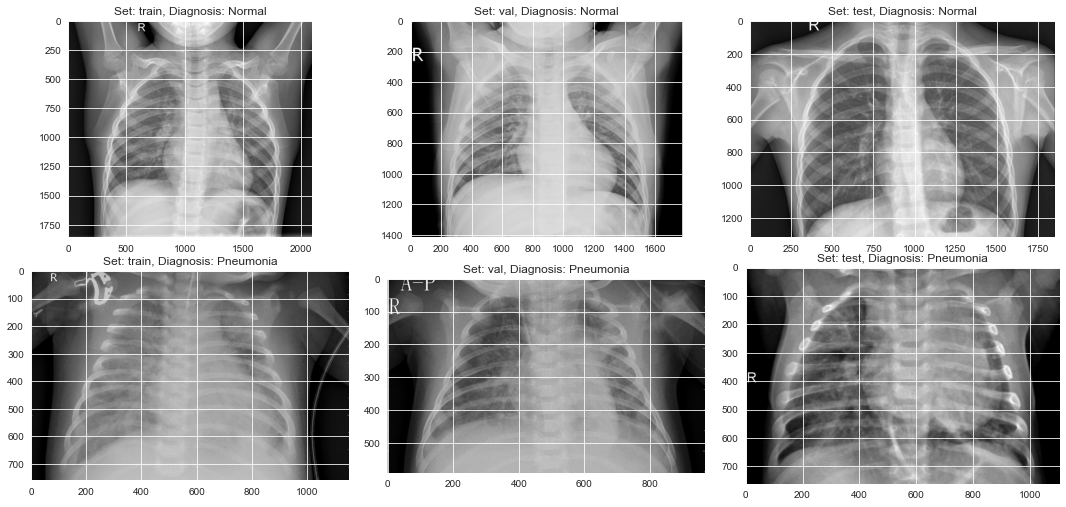

During my studies I've decided to use deep learning neural networks to build an algorithm that classifies a set X-rays images belonging to pediatric patients to help determine if whether or not pneumonia is present. The goal is to help the patient by knowing sooner than later if pneumonia is present so that treatment could begin promptly. The Neural Network I've chosen was the Convolutional Neural Network (CNN) since it is highly preferred for image processing.

For my project I've used data sourced from kaggle.com. Upon initially exploring the data, I noticed it contained 5,756 X-ray images.

After preprocessing the data (I've used image rescaling as well as data augmentation -- this is the process of "augmenting" the data by artificially creating new training data from the existing data by applying a number of techniques such as flipping, zooming, etc.), I've built my model by doing the following: